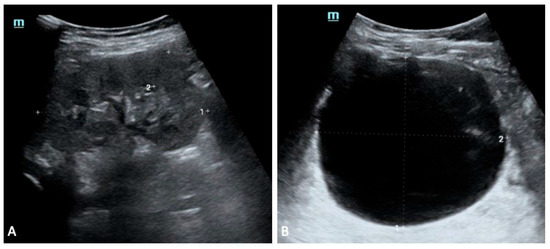

Background: The 17q12 recurrent deletion syndrome is a genomic disorder encompassing a 1.4 to 1.5 Mb region that includes the HNF1B gene, and it manifests with remarkable phenotypic variability. Renal anomalies, endocrine and metabolic disturbances, and neurodevelopmental or psychiatric disorders are recurrent features, [...] Read more.

Background: The 17q12 recurrent deletion syndrome is a genomic disorder encompassing a 1.4 to 1.5 Mb region that includes the HNF1B gene, and it manifests with remarkable phenotypic variability. Renal anomalies, endocrine and metabolic disturbances, and neurodevelopmental or psychiatric disorders are recurrent features, although penetrance and severity differ widely between patients. Methods: We reviewed the literature on the molecular basis, clinical presentation, diagnostic approaches, and management of 17q12 deletion syndrome, and we illustrate the variability of this condition through two contrasting paediatric cases. Results: The cases concern three siblings harbouring the same familial deletion, who nevertheless exhibited striking intrafamilial variability, ranging from renal and neurodevelopmental features to multisystemic involvement. These cases exemplify both extremes of the syndrome and highlight the challenges of clinical prognostication. Conclusions: The review and cases emphasise the importance of early genetic testing in paediatric renal anomalies, the necessity of multidisciplinary surveillance even in asymptomatic individuals, and the relevance of 17q12 deletion as a model of variable expressivity in genomic medicine. Full article

Show Figures

Figure 1